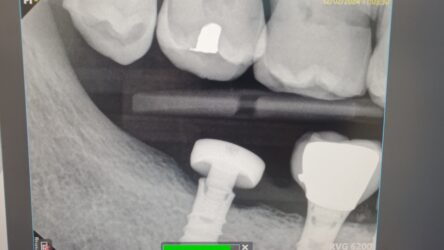

I have a patient with a fractured Straumann tissue-level implant at site #31. The coronal portion of the implant has fractured off circumferentially, leaving only the bone-level portion intact. This implant previously supported a gold crown on a one-piece abutment. Additionally, the tissue-level implant at site #30 has a worn and fractured crown that needs replacement.

let me also clarify the PA. that is a Closed tray impression coping screwed on to the fractured implant.

Heres some additional imaging and info. #30 is also straumann tissue level crown that needs replacing. a healing abutment was placed on #31. you can see a void where the platform broke off. the abutment is only secured by the end of the abutment screw.

our initial plan is to make new crowns #31/30 and splint. hopefully a custom cast abutment #31 if we can find a lab to do it.